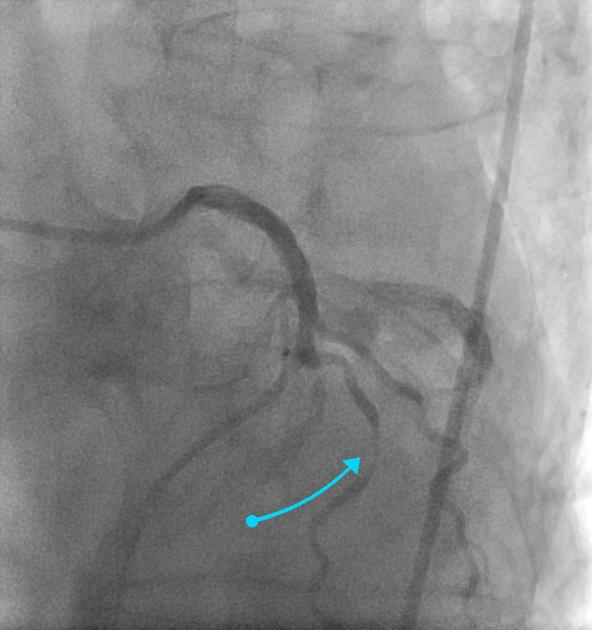

Puzzle 48 annotated

What's the Diagnosis?